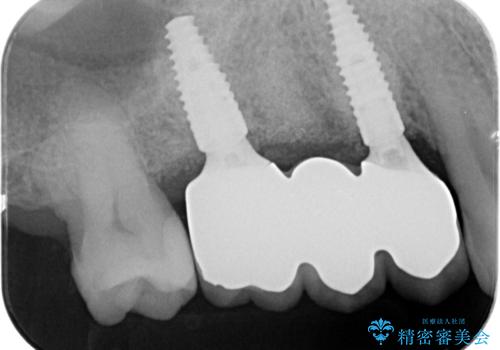

3本の歯が失われた状態を、2本のインプラントで支えるブリッジでの咬合機能回復を計画します。

- 150万円(インプラント×2・チタンカスタムアバットメント×2・ジルコニアクラウン×3・仮歯×3)費用は治療当時の料金となります

歯を失ってから長い期間が経過していたので、仮歯が入り咬合機能が回復できた際に大変喜んでいただくことができました。